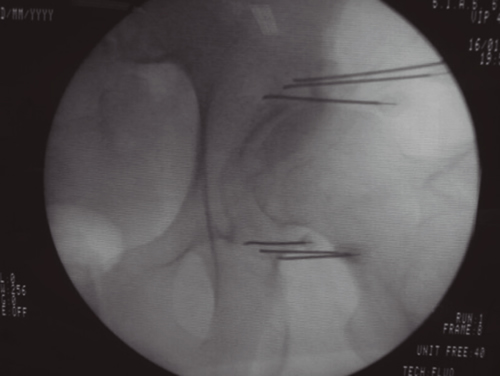

COXARTROSIS

Fig. 3.

La neurotomía por radiofrecuencia de las ramas articulares de los nervios femoral y obturador es una técnica no estandarizada, cuyas referencias anatómicas y radiológicas están todavía sin establecer y que precisarán de la realización de RCT de calidad para poder conseguir datos de evidencia sobre su utilidad. En mi opinión la realización de lesiones en empalizada con dos o tres agujas puede mejorar la posibilidad de lesionar la mayoría de las ramas sensoriales que, debido a las variaciones anatómicas, pueden ser difíciles de lesionar con una sola aguja. El principal peligro y complicación de esta técnica es la aparición de hematomas por punción accidental de la arteria femoral, si el abordaje se hace de manera vertical. La técnica se puede realizar con control radiológico o ecográfico, ofreciendo la ecografía la ventaja de poder visualizar el paquete vasculonervioso femoral.